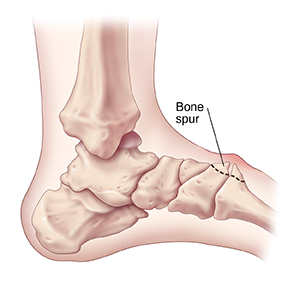

Midfoot joint spur

To get rid of the bump, the spur is removed on both sides of the joint. You can bear weight on your foot right after surgery. You'll need to wear a surgical shoe for a few weeks.